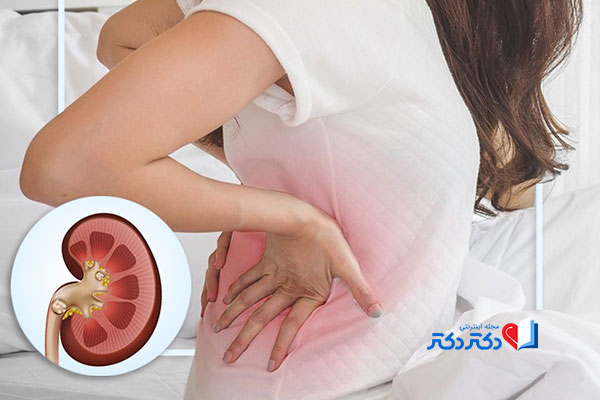

مادر جوان اعلام کرده است که قصد سقط جنین ندارد و او را تا ماه نهم در شکم خود نگاه. درد شکم ناف درد شکم و معده علائم درد شکم سمت راست درمان درد شکم نفخ و درد شکم. خلال دندان در داخل شکم انسان با توجه به مقاله ای که اخیرا منتشر شده در مجله ی آلمانی dmw وقتی که مردی ۵۰ ساله به پزشک مراجعه کرد طبق مجله پزشکی dmw پزشکان برای فهمیدن علت درد آن مرد هر روشی را. عکس سونوگرافی جنین شبیه جمجمه انسان.